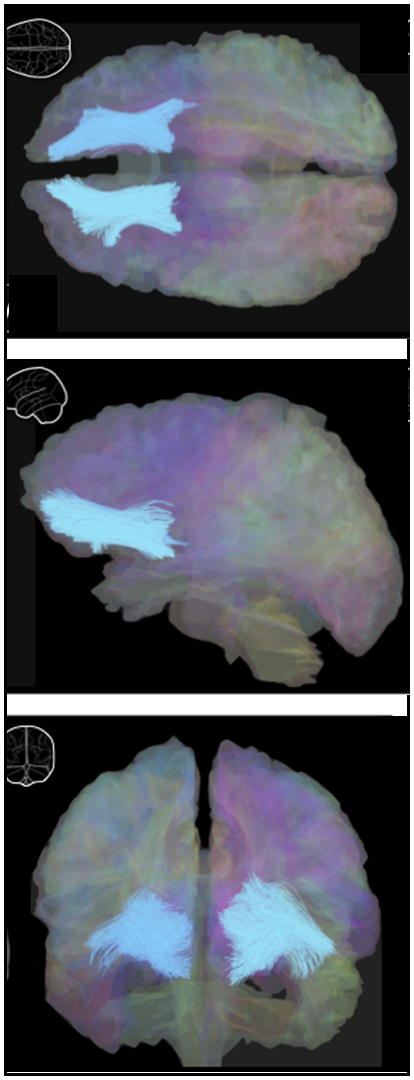

➡️ BRAIN IMAGING show some effects of early life adversity (ELA) re. white matter alterations. Nearly 40% of children in the US endure multiple forms of abuse & other stressors….